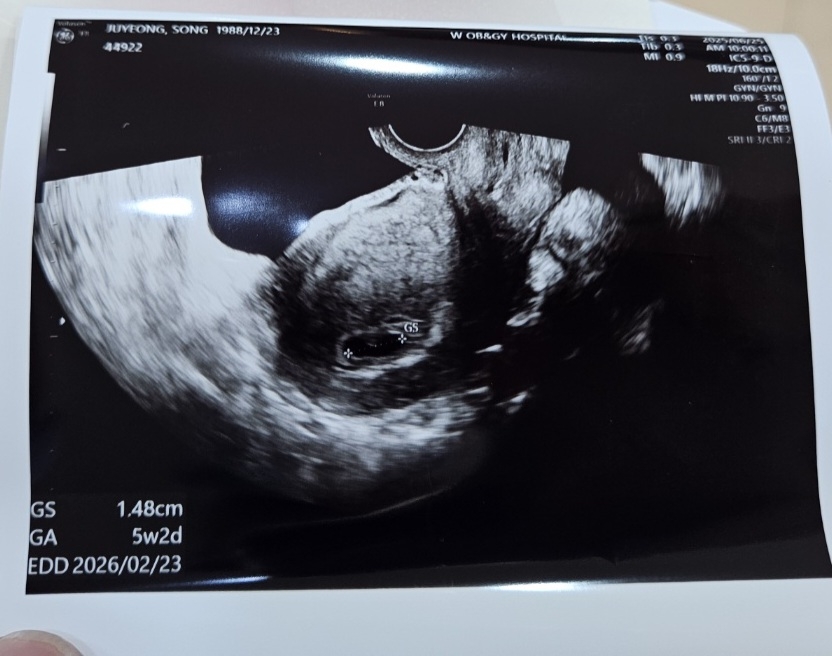

아기집 모양

아기집 모양 괜찮나요? 5주 2일인데 갑자기 갈색 분비물 비침 있어서 아침에 갓는데 아기집 모양이 안 좋다고, 난황은 아직이구요... 난황은 다들 언제 생기셨나요 ? 혹시 이런 모양 아기집 이신 분 있으셨나요

네 전 난황이 아직 안보여서.. 걱정이네요.. 아기집 모양도 그렇다고 해서.. 제가 보기엔 괜찮은 거 같은데 ㅠㅠ 난황이 좀 더 늦게 생기는 경우가 있다고 해서 기다리려구요